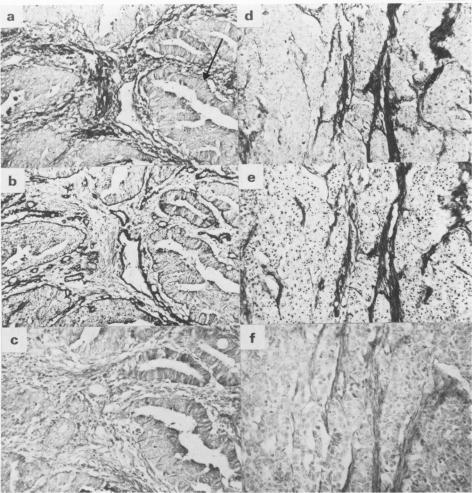

Using an immunoperoxidase procedure, we have examined the distribution of laminin and fibronectin in normal human large intestinal mucosa and in 50 cases of rectal adenocarcinoma for which extensive clinical follow up was available. In normal tissue, laminin staining was largely restricted to basement membranes, including that underlying the epithelial cells, whereas fibronectin was found in both basement membranes and surrounding connective tissue. In rectal carcinomas, basement membrane-like staining for laminin associated with tumour cells was found in only 27 out of the 50 cases studied. Statistical analysis showed that the presence of laminin-containing basement membranes was correlated with low histological grade (well-differentiated tumours), but not with stage (progression through the bowel wall and the development of lymph node metastases) and, in a highly significant way, with a reduced incidence of distant metastases and increased patient survival. Although fibronectin was found in tumour cell basement membranes where these were present, it was also found in the stroma of all 50 tumours. There was no apparent correlation between the presence of stromal fibronectin and grade, stage or development of metastases. Finally, attention is drawn to some of the technical difficulties in detecting basement membrane antigens in formalin-fixed tissue, the material most frequently available for retrospective study.

我们采用免疫过氧化物酶法,研究了层粘连蛋白和纤连蛋白在正常人大肠黏膜以及50例有广泛临床随访资料的直肠腺癌中的分布情况。在正常组织中,层粘连蛋白染色主要局限于基底膜,包括上皮细胞下方的基底膜,而纤连蛋白则在基底膜和周围结缔组织中均有发现。在直肠癌中,在所研究的50例病例中,仅有27例发现与肿瘤细胞相关的层粘连蛋白呈基底膜样染色。统计分析表明,含层粘连蛋白的基底膜的存在与低组织学分级(高分化肿瘤)相关,但与分期(肿瘤穿透肠壁及发生淋巴结转移)无关,且与远处转移发生率降低及患者生存率提高高度相关。尽管在存在肿瘤细胞基底膜的地方发现了纤连蛋白,但在所有50例肿瘤的基质中也都发现了纤连蛋白。基质纤连蛋白的存在与分级、分期或转移的发生之间没有明显关联。最后,需要注意在福尔马林固定组织(这是回顾性研究最常用的材料)中检测基底膜抗原存在一些技术难题。